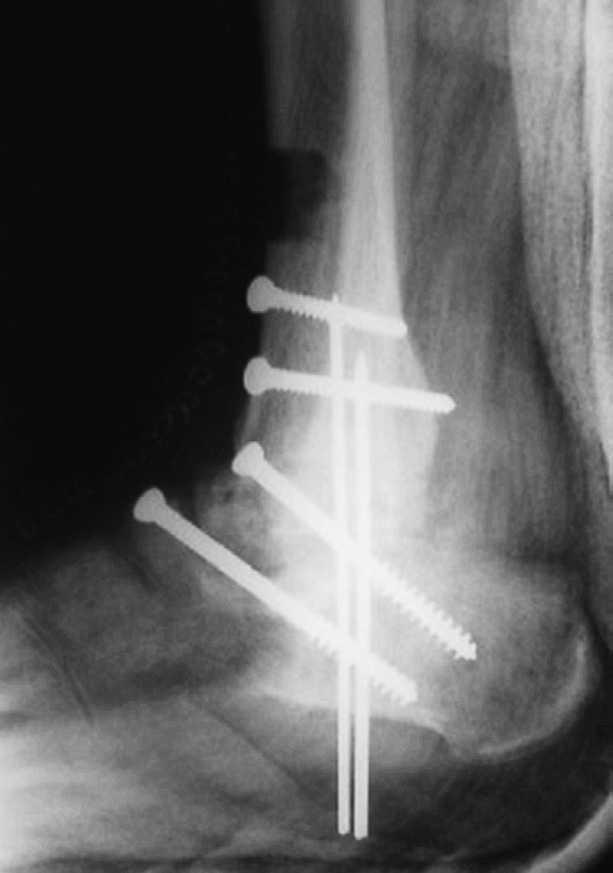

Se observaron 2 (5,26%) casos que precisaron de varias reintervenciones y lavados con el procedimiento de Papineau en 3 tiempos (fig. 11).

Fig. 11. --Osteomielitis. Técnica de Papineau en 3 tiempos. Resultado a los 24 meses. Artrodesis consolidada sin infección.

Fig. 11. --Osteomyelitis. Papineau's technique in 3 stages. Results at 24 months. Consolidated arthrodesis without infection.

Hemos realizado tan sólo 1 caso debido a una pseudoartrosis (figs. 11 y 12), que se complicó posteriormente con una osteomielitis aguda por lo que se le realizó los 3 tiempos de Papineau. En líneas generales, la talectomía no ha demostrado buenos resultados.

Fig. 12. --Pseudoartrosis y NAV en fractura de cuello de astrágalo. Artrodesis tipo Blair

Fig. 12. --Pseudoarthrosis and avascular necrosis in a fracture of the astragalus neck. Blair-type arthrodesis.